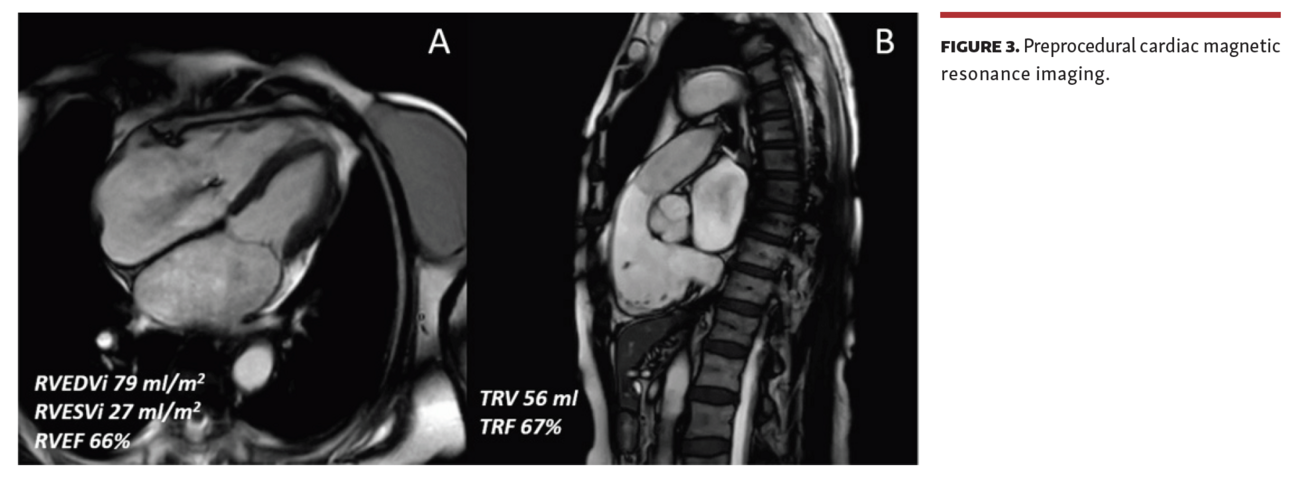

The preprocedural cardiac magnetic resonance (CMR) showed a right ventricular end-diastolic volume index (RVEDi) of 79 mL/m2, right ventricular end-systolic volume index (RVESi) of 27 mL/m2, tricuspid regurgitant volume (TRV) of 56 mL, and tricuspid regurgitant fraction (TRF) of 67% (Figure 3). Due to the patient's history of breast cancer radiotherapy and high surgical risk, the heart team preferred a transcatheter approach as the treatment option. The first TriClip (Abbott Vascular) was successfully implanted in the anteroseptal commissure, determining annulus size reduction and the subsequent necessity of transesophageal echocardiographic projection change to assess the result due to acute reshaping (Figure 4 and Figure 5; Video Series). A second TriClip was implanted in the anteroseptal commissure, highlighting the changes in the valvular plane and cardiac axis (Video Series). Residual TR was trivial (Video Series). The acute remodeling was confirmed at the CMR follow-up (Figure 6), with significant volume and TR reductions (RVEDi, 39 mL/m2; RVESi, 18 mL/m2; TRV, 8 mL; and TRF, 23%).